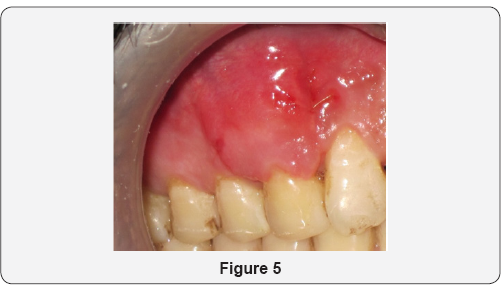

Patient aged 34 years reported to the department of Periodontology with the complaint of long corner tooth with sensitivity. On clinical examination, gingival recession was observed on maxillary right canine (Figure 1). Diagnosis was made as Miller's Class I gingival recession with 13. Coronally advanced flap with alloderm with microsurgical approach was planned. Patient's consent as well as ethical clearance was obtained prior to the surgical intervention. Following administration of local anesthesia, the tooth with the recession was root planed. A split-thickness flap with two vertical releasing incisions with micro scalpels was raised with microelevaters, and the papillae were de-epithelialized (Figure 2). Alloderm was measured, cut and rehydrated before suturing it with chromic gut 5-0 covering the defect as shown in Figure 3. The flap was coronally moved and secured to the de-epthelialized papillae over the alloderm with interrupted sutures (5-0 black braided silk) as shown in Figure 4. Pressure was applied before placing the periodontal dressing on surgical wound. Sutures were removed on 10th day and healing was found to be satisfactory (Figure 5). Healing is generally uneventful in minimally invasive surgery. Patient was evaluated after 3 months; there was 100% coverage of a denuded root with satisfactory gingival thickness and color match with microsurgical reconstruction of lost gingival (Figure 6).